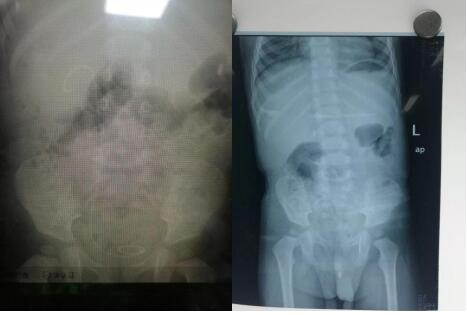

男同视频 泌尿外科成功为一岁半患儿实施 尿道结石钬激光碎石术